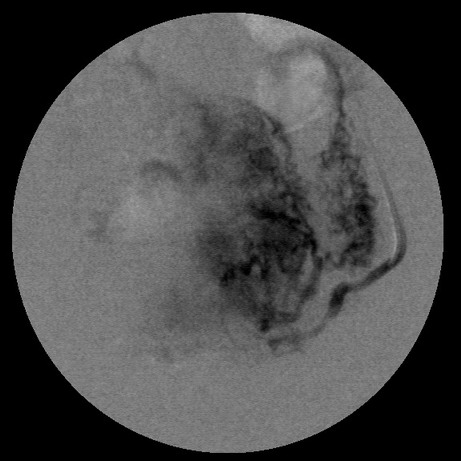

女,35岁,子宫多发肌瘤

子宫动脉增粗,分支数量增多,迂曲,染色明显并排空延迟

栓塞剂用的是进口pva,二瓶,几千块呀,栓塞面积应该不大吧,呵呵